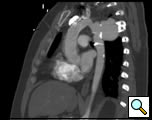

The patient is a 33 year old male with a history of juxtaductal coarctation who underwent a repair early in infancy. The patient had a recurrence of the coarctation and underwent a second open repair and left diaphragm plication at 2 years of age. He was lost to follow-up until recently when he presented to an emergency room with a several week history of hemoptysis and left back pain. The patient’s physical exam was remarkable only for a well-healed left thoracotomy incision. The patient was afebrile with equal blood pressures in all 4 extremities. The patient’s white count was normal. A CT scan of the chest demonstrated a saccular aneurysm of the proximal descending thoracic aorta measuring approximately 6cm in diameter (Figure 1). The patient was transferred to the Oregon Health and Sciences University for further management.

At our institution a dedicated CT angiogram of the chest was obtained to better define the morphology of the patient’s arch and aneurysm. This confirmed the finding of a saccular aneurysm just distal to the left subclavian artery takeoff. Because of the patient’s prior history of coarctation recurrence and repair, this was felt most likely to represent a pseudoaneurysm, possibly at the site of a patch repair. Aortic reconstructions of the CT angiogram showed no evidence for recurrence of the coarctation (Figure 2). There was, however, a size discrepancy in the diameter of the aorta above and below the aneurysm. The diameter of the aortic arch between the left carotid and left subclavian arteries was 13mm. The diameter of the descending thoracic aorta distal to the aneurysm was 23mm.